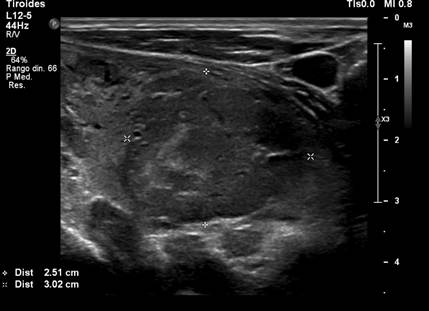

We present the case of a 69-year-old man with a history of hypertension and stage III chronic kidney disease, who in 2017 underwent left radical nephrectomy for clear cell renal carcinoma (pT1bN1M0, Fuhrman histological grade III). During oncological follow-up, the patient remained asymptomatic, with a normal physical examination. A positron emission tomography (PET-CT) scan incidentally revealed a hypometabolic thyroid nodule (SUVmax [2,6]), prompting the recommendation for monitoring. Subsequently, in 2022, asymptomatic primary hypothyroidism was diagnosed without palpable findings, and treatment with levothyroxine 50 mcg/day was initiated. Two years later, a cervical ultrasound revealed a 3.5 x 2.5 x 3 cm hypoechoic solid nodule with irregular margins, cystic components, and mixed vascularization, located in the lower pole of the left lobe, classified as TIRADS 4C (Figure 1), which was palpable. A fine-needle aspiration biopsy (FNAB) of the nodule was performed and yielded a Bethesda category III.

Figure 1

Cervical ultrasound. Heterogeneous thyroid nodule measuring 3.5 x 2.5 x 3 cm.

Source: SOLCA Intranet - Guayaquil.